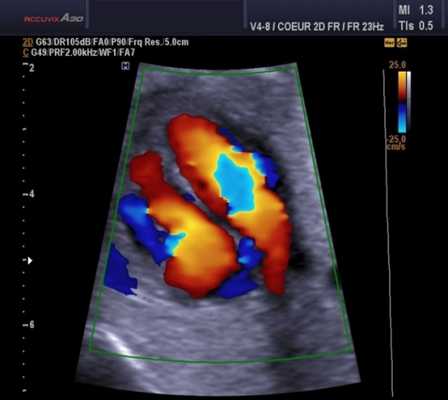

Регургитация. Она может происходить через отверстие клапана (чрезклапанная) или вокруг пришивного кольца (парапротезная). Легкая транскалапанная митральная регургитация может быть обнаружена в нормально функционирующих клапанах, чаще в механических клапанах. Это связано с закрытием клапана или из-за зазоров между разными частями протеза. Ее бывает трудно обнаружить из-за маскировки тенью протеза. Умеренная или тяжелая митральная регургитация всегда считается патологической.

Непрерывно-волновой допплер более полезен, чем импульсный, а цветное допплеровское картирование кровотока (ЦДК) хорошо для отображения антероградных и ретроградных потоков. Турбулентный кровоток регистрируется в виде мозаики цветов. В митральных биопротезах обычно видна одна струя. В большинстве митральных механических клапанов видны 2 струи (почти равного размера у клапанов Старра - Эдвардса, одна меньше другой в клапанах Бьорка - Шайли).

При регургитации может быть несколько струй разного размера в зависимости от типа клапана (например, 2 струи у Бьорка - Шили, несколько у Старра - Эдвардса). ЦДК также помогает различать чресклапанную и парапротезную регургитацию и помогает выявить новую регургитацию.Проведение эхокардиографии при неисправности протезного клапана